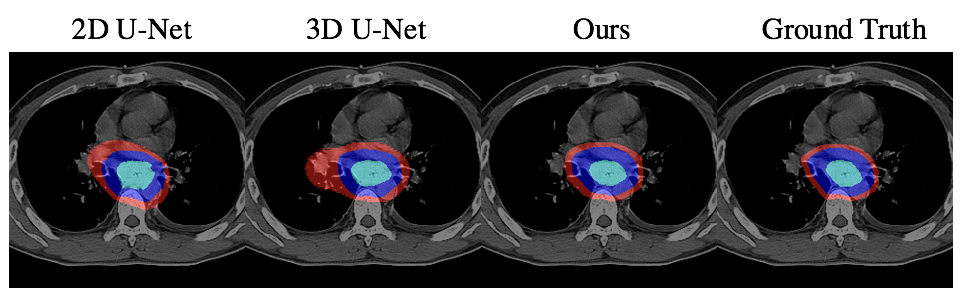

To evaluate our method, we chose the most commonly used CNN-based segmentation frameworks: 2D U-Net[8] and 3D U-Net[4] as our baselines. Since we focus on predicting the accurate radiotherapy target contouring, we trained and tested with valid slices that contain tumors. That is, given the volume where oncologists want to deliver radiation, we are able to segment the GTV, CTV and PTV regions precisely. For quantitative comparison, following metrics in [5], we use DSC, Sensitivity, and Specificity and ran with five-fold cross-validation. Table. 1 and Figure. 2 shows that our non-interactive method outperforms all the baselines both qualitatively and quantitatively. In the interactive setting, the results are evaluated on the selected sequences with “min median DSC” of GTV for each patient, in the exclusion of the slice we have reconstructed the features. As shown in Table. 2, the results are further improved after the interaction.